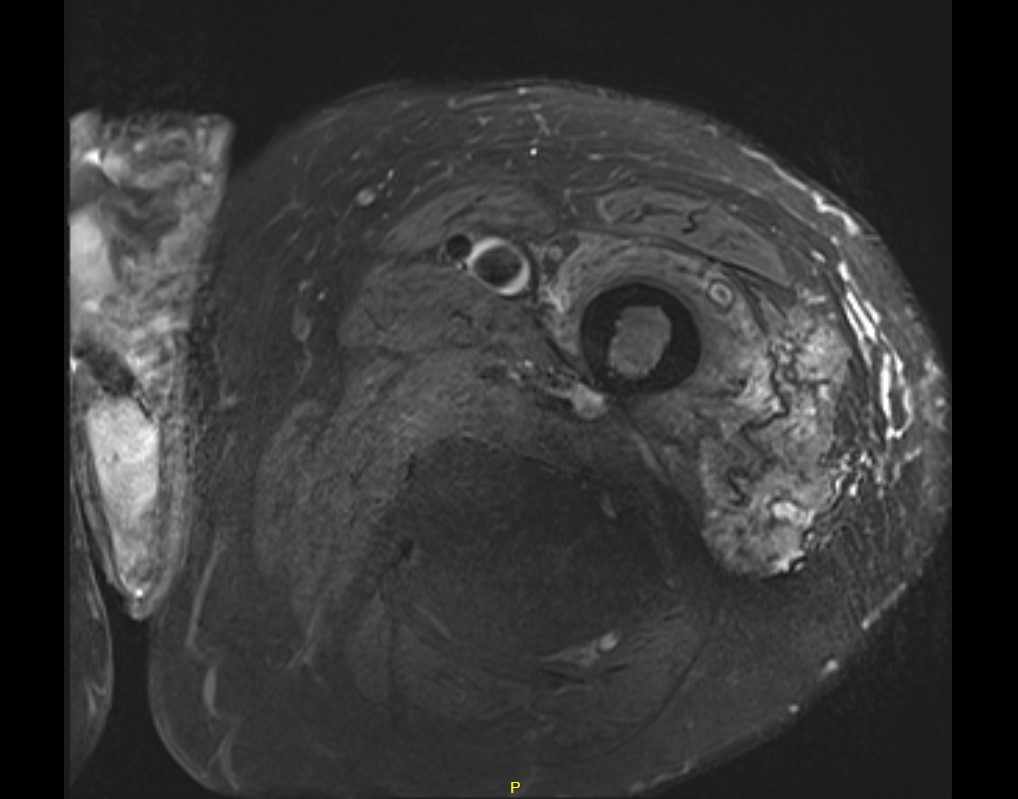

MRI

Deep to fascia / heterogenous

Liposarcoma pelvis

Liposarcoma vs Atypical Lipoma

Liposarcoma

- > 5 cm

- rapidly growing

- deep to fascia

- non homogenous on MRI